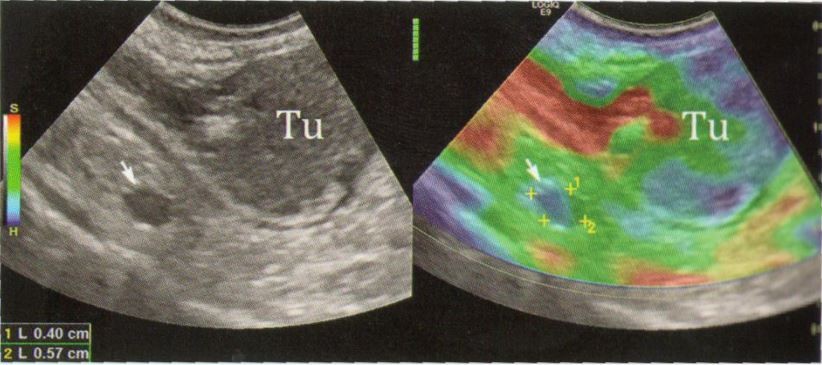

Este o metodă nouă pentru depistarea cancerului tiroidian şi mamar. Între leziunile canceroase şi cele necanceroase există o diferenţă de duritate şi elasticitate care poate fi cuantificată cu ajutorul elastografiei.

Nodulul malign (cancerul) este de peste 10 ori mai dur decât nodulul benign (necanceros), acest lucru fiind pus în valoare cu ajutorul elastografiei. Nodulii depistaţi maligni prin elastografie sunt în proporţie de 70 - 80% cancere.

Prin elastografie se poate aprecia şi suprafaţa de extindere a ţesutului canceros care de cele mai multe ori este mai mare decât cea palpabilă sau vizibilă prin ecografia obişnuită, sporind în felul acesta şansele de reuşită a intervenţiei chirurgicale.